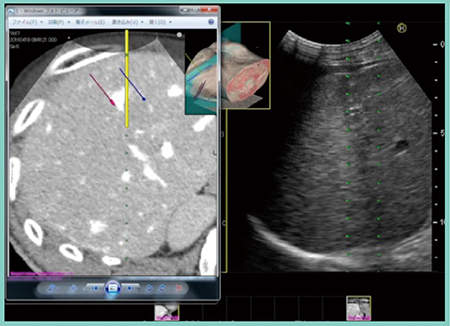

シミュレーションは前述の方法にて人工腹水を併用して治療前日に行い,当日はリファレンス画像を参照しながら,まずは北半球の穿刺を行った(図3,4)。その後,画面表示をReal-time Biplaneに切り替え,凝固域の広がりを見ながら穿刺位置を微調整しつつ焼灼した。続いて南半球も同様に穿刺(図5),焼灼を行い,最後に凝固域の分裂がないことを確認した。治療後のCTでは,凝固域がほぼ球形を成し,コロナ濃染も含めて十分なマージンを形成できていることが確認できた。

図4 実証試技における北半球の平行穿刺

図5 実証試技における南半球の穿刺